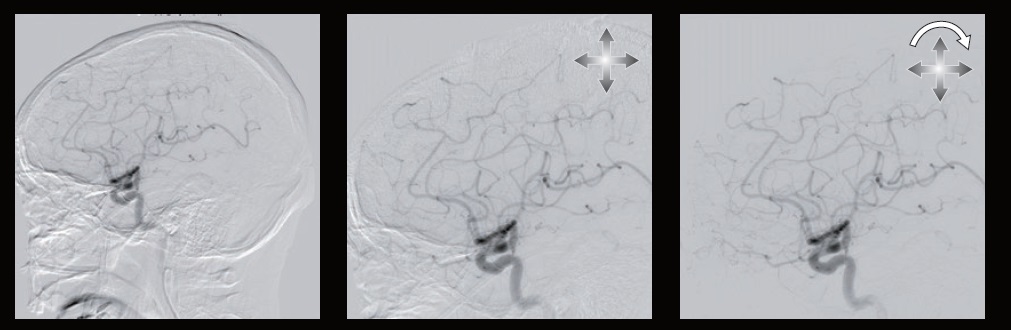

Двопроекційна (біплан) ангіографічна система з унікальною С-аркою на підлозі та вибором розміру детектора в залежності до потреб відділення.

Забезпечуючи неперевершений гнучкий доступ до пацієнта, п'ятиосьова система з кріпленням на підлозі та Ω-арка з кріпленням на стелі ідеально підходять для інтервенційних процедур в нейрохірургії та кардіології, особливо дитячій.

Технологія детектору високої роздільної здатності

Новий, технологічно вдосконалений детектор високої чіткості Canon Medical покращує візуалізацію та збільшує просторову роздільну здатність, щоб під час інтервенційних процедур працювати максимально безпечно та інформативно.

Унікальний гібридний 12-дюймовий (30 см) розмір плоского детектора Canon Medical забезпечує просторову роздільну здатність до 2,5 разів більше. Такі режими збільшення як 3 дюйми (8 см), 2,3 дюйми (4,5 см) та 1,5 дюйми (4 см) тепер можна отримати із неймовірно хорошою роздільною здатністю зображення.

Об'єктивно завдяки більшій роздільній здатності в режимі Hi-Def зображення виходять більш чіткими та якіснішими, ніж зображення в режимі FPD.

Технічно: за першої ж необхідності збільшення з високою роздільною здатністю:

Автоматичний зсув пікселя

Автоматичне виправлення зсуву положення маски зображення, що був спричинений рухом тіла під час DSA або 2D roadmap. Автоматичний зсув пікселів в режимі реального часу автоматично коригує положення зсуву.

Ця функція автоматично активується після отримання зображення. Для застосування цієї обробки не потрібні дії оператора.